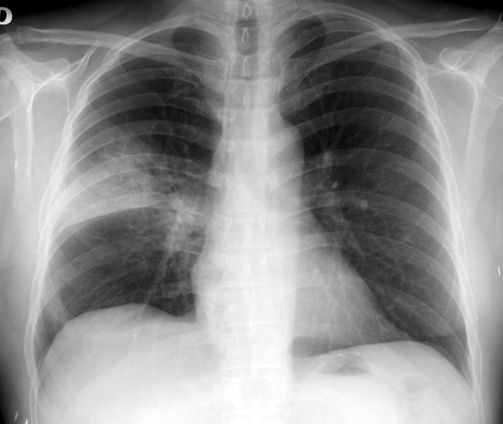

Neumonías adquiridas en la comunidad en pacientes con enfermedad pulmonar obstructiva crónica tratados con corticoides inhalados u otros broncodilatadores. Estudio PNEUMOCORT

Aten Primaria. 2018. No hubo diferencias entre cohortes en el riesgo de neumonía adquirida en la comunidad (NAC) ni exacerbaciones graves. Las exacerbaciones leves fueron superiores en el grupo corticoides inhalados (CI). Tanto NAC como exacerbaciones graves fueron más frecuentes en pacientes con EPOC grave y en pacientes tratados con dosis altas de CI.

Neumonía adquirida en la comunidad: actualización

Boletín INFAC, Información farmacoterapéutica de la Comarca, vol 24 nº 5, 2016